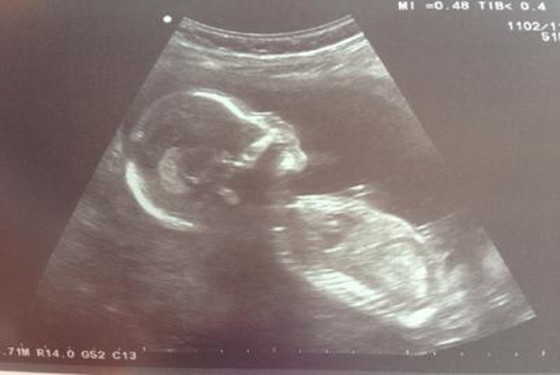

我是八月二十八,农历七夕的预产期。八月二十六八点整顺产男宝,医生说当天晚上二十几个孩子,只有两个女宝,这些小子们连个青梅竹马都得抢……孕期一直猜是男是女,没有问过B超医生,总结下我的症状,仅供娱乐……

10、B超显示宝宝脸朝外的男,面对妈妈的女;不准,说是脸朝左边